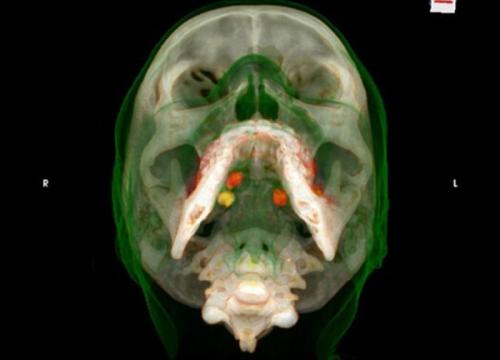

Рентгеновские снимки «лошадок» - людей, перевозящих небольшие партии наркотиков внутри своего тела. Если контейнеры с наркотиками раскрываются - человек умирает.

Кокаин под языком.